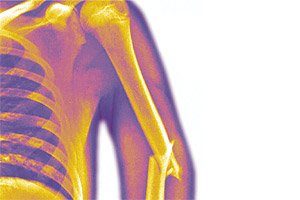

Published in Lesiones de huesos